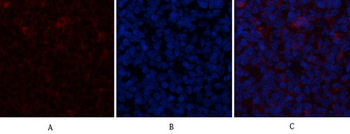

α-SMA Polyclonal Antibody [orb1410980]

IF, IHC-P, WB

Human, Mouse, Rat

Rabbit

Polyclonal

Unconjugated

100 μlα-SMA Polyclonal Antibody [orb1411649]